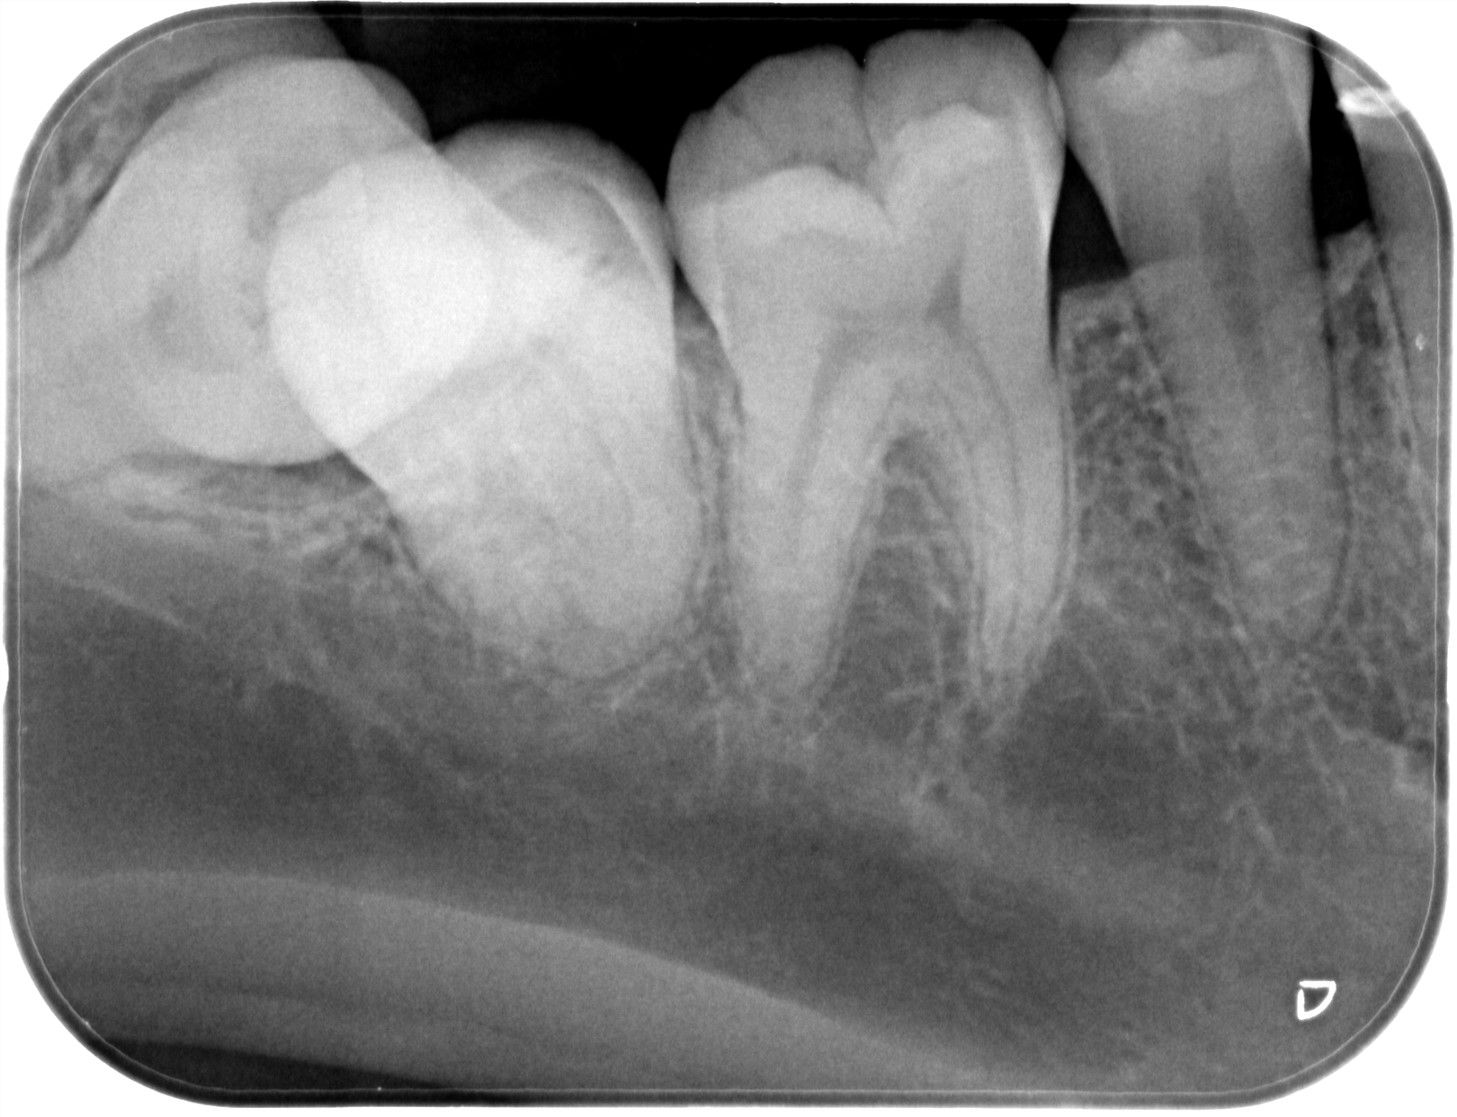

他院にて虫歯治療を行い神経治療が必要であると診断されましたが、

根管が複雑な形をしているため治療が難しいと言われたとのことで

当院のホームページをみて来院されました。

当院にて診査診断を行い専門医による根管治療を行いました。

治療前と治療後の比較

Before